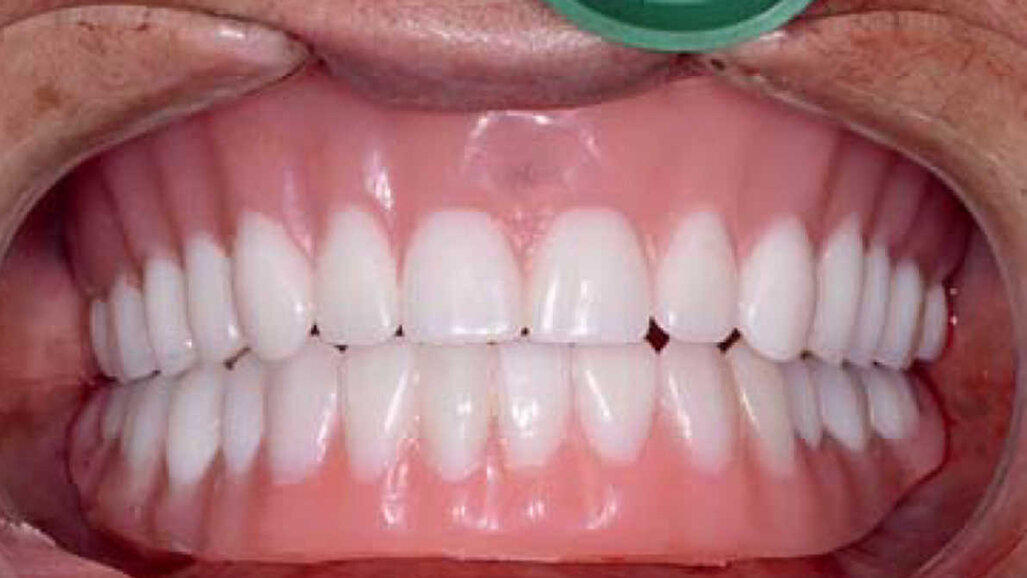

Les restaurations définitives ont été mises en place au cours de la visite suivante et montraient une adaptation, une fonction et une relation inter-occlusale précises (Figs. 21 et 22). Grâce à la phase d’essayage, aucun ajustement des prothèses en zircone monolithique n’a été nécessaire, car les bridges en PMMA avaient permis de définir précisément les modifications nécessaires à l’obtention de la forme et de l’esthétique parfaites. Une dernière radiographie a confirmé l’adaptation totale des restaurations en zircone BruxZir sur les piliers implantaires personnalisés Inclusive. La patiente s’est montrée extrêmement satisfaite de la reconstruction de ses arcades maxillaire et mandibulaire dont le rétablissement de l’esthétique et de la fonction dentaire lui avait rendu confort et confiance.

Fig-21-Vue-des-dents-non-engrenées-300x300-